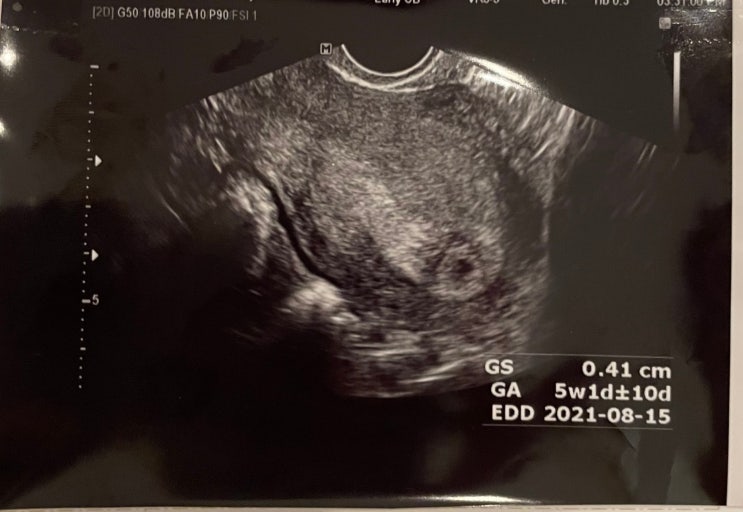

임신초기 5주~10주 증상 / 입원 / 피고임 / 입덧 / 임산부속옷

갑작스런 임신 평소 날음식을 엄청 좋아하는 나 (생선회, 육회 등) 겨울 제철음식인 대방어회와 석화를 사...